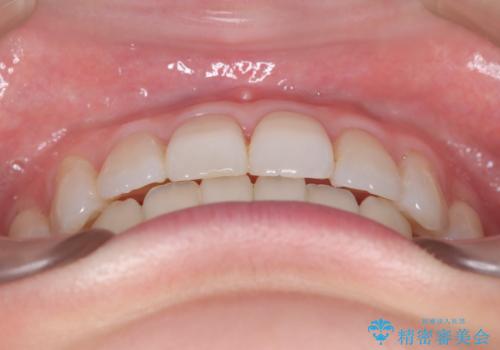

前歯の叢生は解消され、自然で調和の取れた歯並びが得られました。

「歯をほとんど削らずにきれいになった」と、患者様にもご満足いただけました。